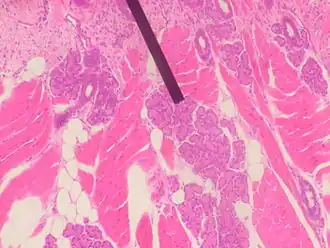

Imagen tomada con un microscopio óptico de un corte histológico de una glándula de Ebner, un tipo de glándula exocrina, teñido con hematoxilina-eosina. | ||

Histología

Las glándulas exocrinas multicelulares mayores presentan ciertas características comunes en todas ellas. Están rodeadas por una capa de tejido conectivo que constituye la cápsula y están divididas en lóbulos por tabiques o septos conjuntivos que se introducen en la glándula a partir de la cápsula.

Los lóbulos a su vez se dividen por delgados tabiques en unidades menores: los lobulillos y todavía en estructuras menores ya no visibles macroscópicamente: los lobulillos microscópicos, en los que el tejido colágeno penetra parcialmente. Los vasos y nervios acompañan en su distribución al tejido conjuntivo.

El producto de secreción se elabora en los ácinos y luego se excreta por conductos intercalares, que se van uniendo para formar conductos cada vez de mayor calibre llamados intralobulillares, después interlobulillares, lobulares y por último forman un conducto principal que desemboca en el exterior o en una cavidad. Estas ramificaciones adoptan la forma como las ramas de un árbol.